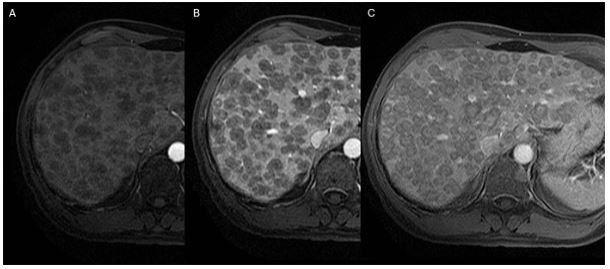

Методы динамического контрастирования печени на МРТ

Раздел: Снимки-подсказки